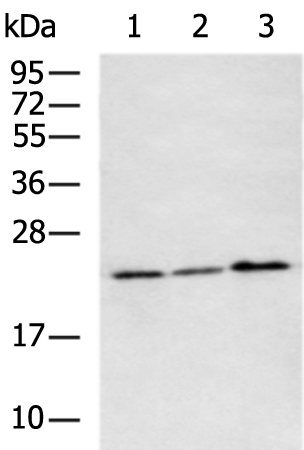

分类: 科研抗体货号: P11280别名: 24p3, MSFI, NGAL应用: WB,IHC反应种属: Human